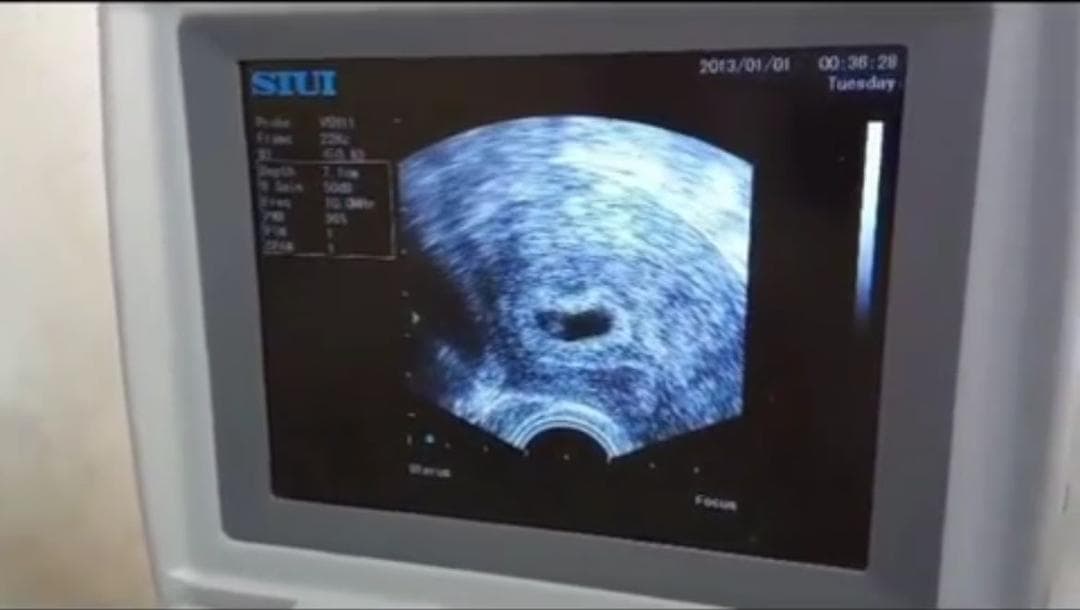

✅ پایشهای دقیق دوران بارداری رحم اجارهای

✅ IVF (لقاح خارج رحمی) با درصد موفقیت بالا